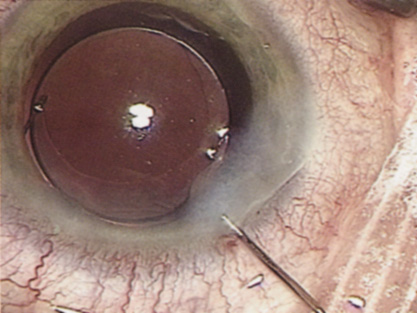

Although slit-lamp examination can give the ophthalmologist an excellent estimate of endothelial health, sometimes a formal assessment of the corneal endothelial cell density is helpful (Fig. 4). This information is most likely to be helpful in advising patients who may be at greater risk of postoperative corneal decompensation. Specifically, patients with cornea guttata, previous ocular surgery, history of blunt ocular injury,56 exfoliation syndrome,57 iridocorneal-endothelial syndromes,58 or a history of glaucoma59 are known to have reduced endothelial cell counts. Patients with a history of acute angle closure are at particular risk because each episode of elevated intraocular pressure can damage endothelial cells.60

There are qualitative and quantitative methods for endothelial cell evaluation. Cell density can be measured directly with an endothelial cell camera. The surgeon also should view the photograph and qualitatively estimate the regularity of the endothelial cell mosaic. Some instruments calculate a coefficient of variability and percent of hexagonal cells.

When an endothelial cell camera is not available, qualitative assessment of count and cell morphology can be accomplished at the slit-lamp using a technique called specular reflection.61 The ophthalmologist focuses a narrow parallelepiped on the corneal epithelium, directing the beam at the periapical cornea from a 45-degree angle. The slit beam is moved slowly from side to side until the bright corneal reflex strikes the examiner's view from the epithelial surface reflection (first Purkinje-Sanson image). On high magnification, the examiner should focus on the endothelial surface just next to the bright reflex. The image of the endothelial mosaic will come into view. The surgeon can make a qualitative assessment of the cell density and degree of regularity. With practice, these estimates can be surprisingly accurate.

The implications of a reduced endothelial cell count are primarily prognostic and can provide the surgeon with more information to help counsel the patient about the risk of corneal decompensation with cataract surgery. Gentle phacoemulsification without triple procedure is recommended when cornea is clear and compact, given that a significant number of patients may be able to avoid a corneal transplant despite uncountable cell densities. However, these patients should be advised that they may be at an increased risk of requiring a corneal transplant.